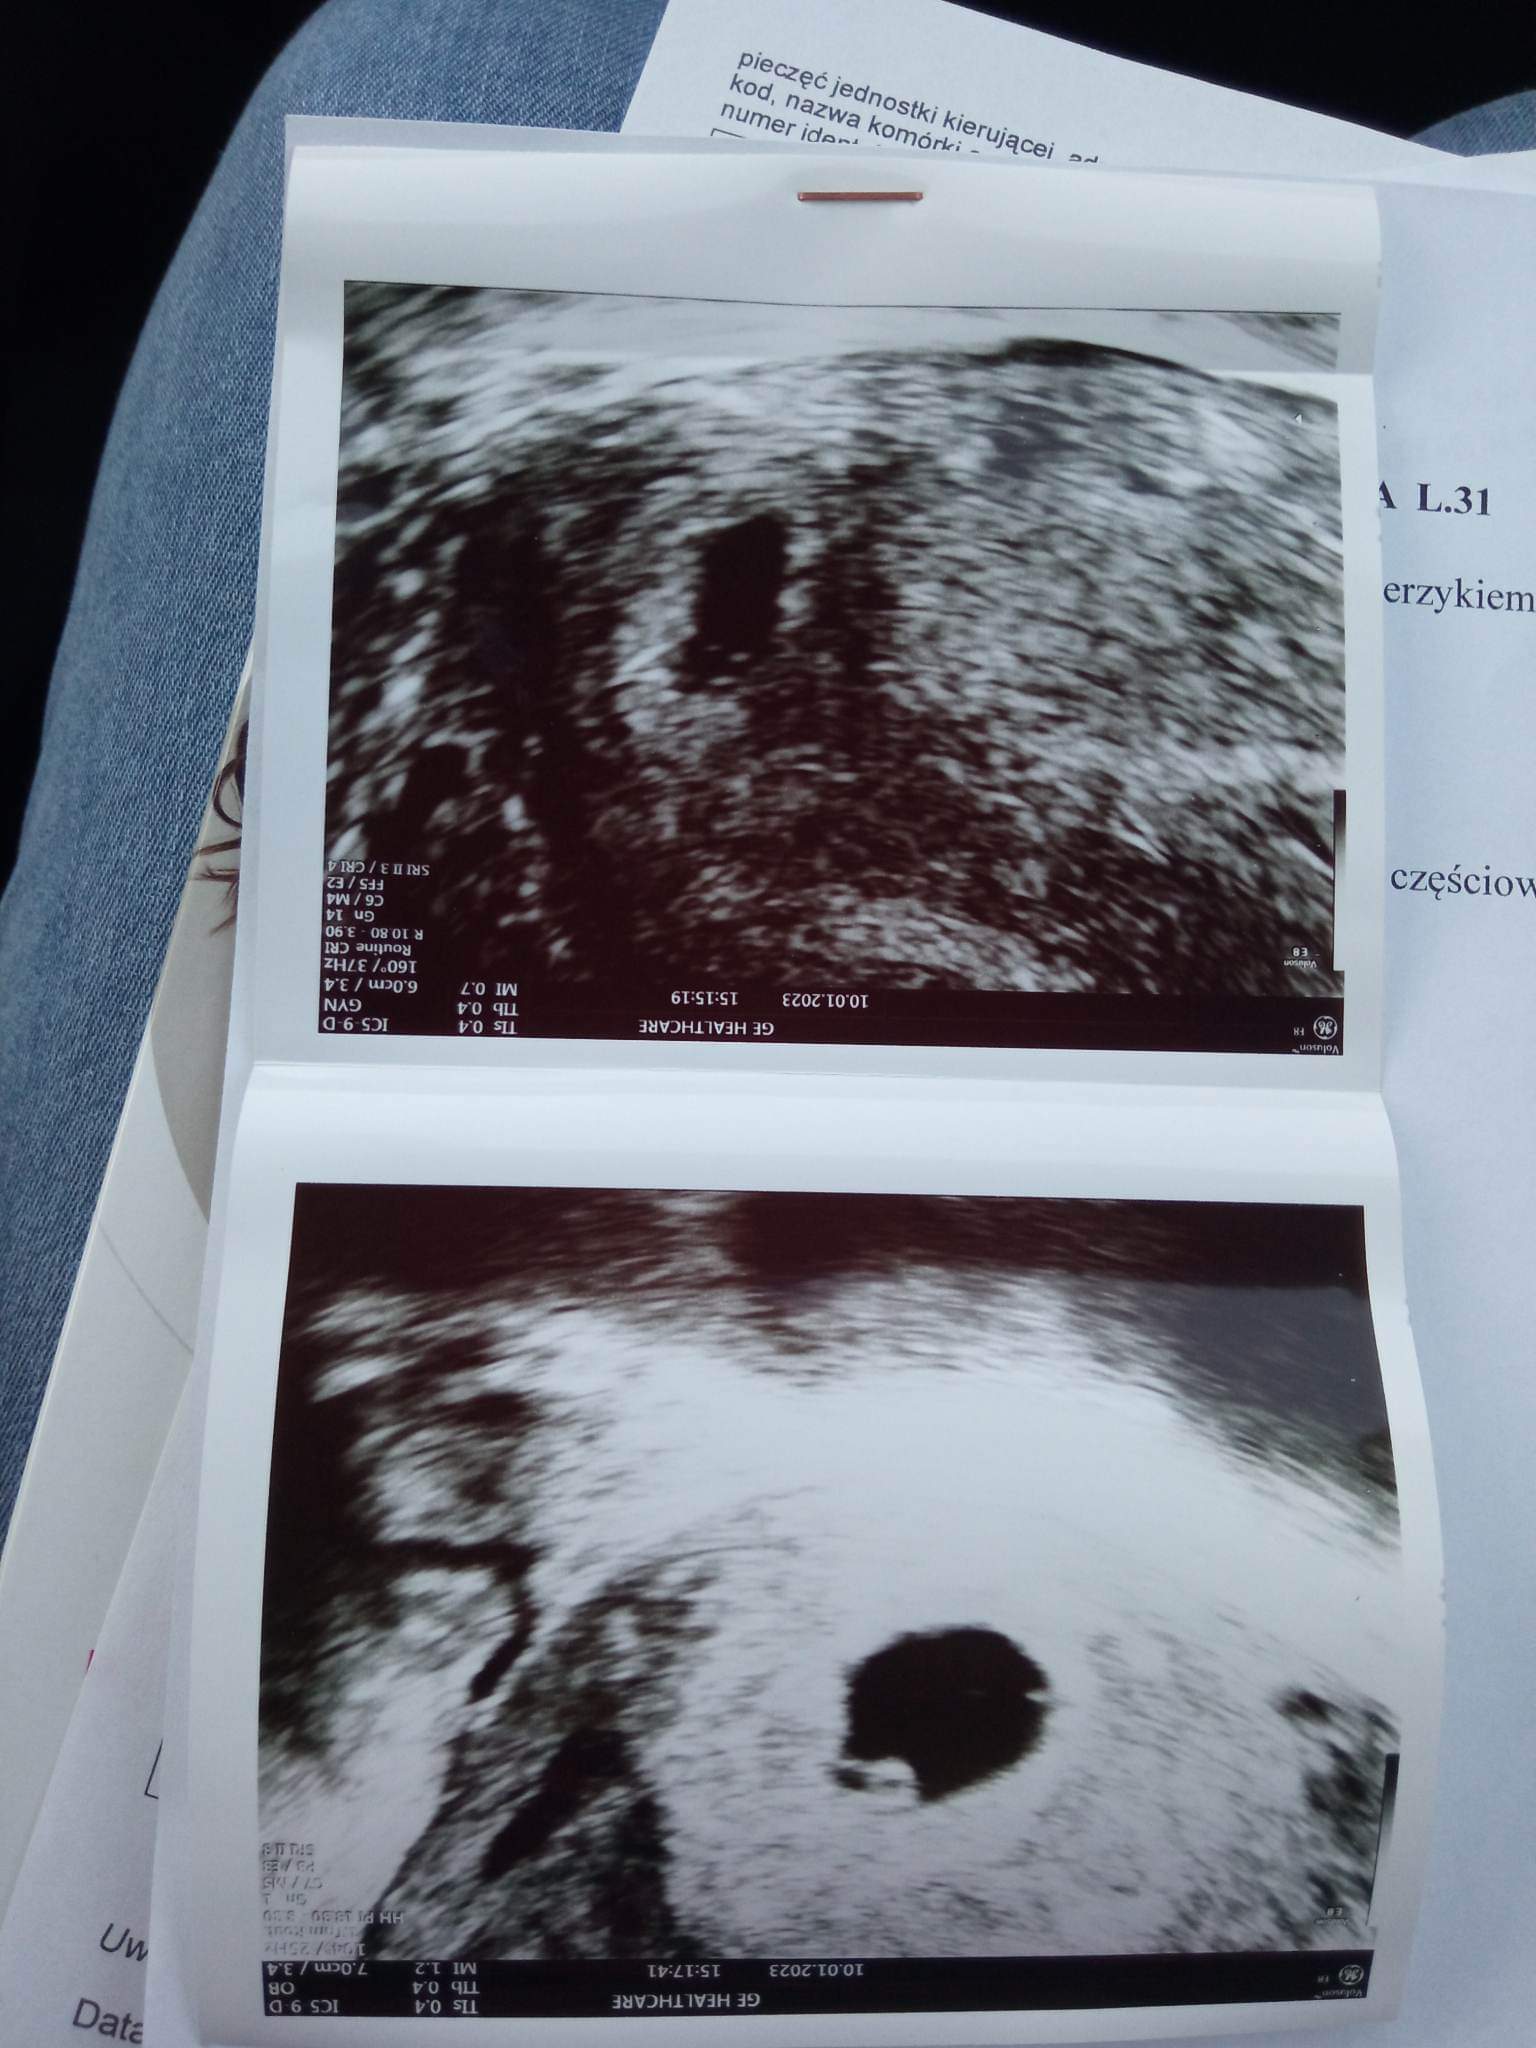

Masz jakieś zdjęcie usg?

Mam takie dwa zdjęcia. Nie wiem które co przedstawia bo na jednym coś jest a na drugim nie

Załączniki

• received_828111574957954.jpeg

received_828111574957954.jpeg